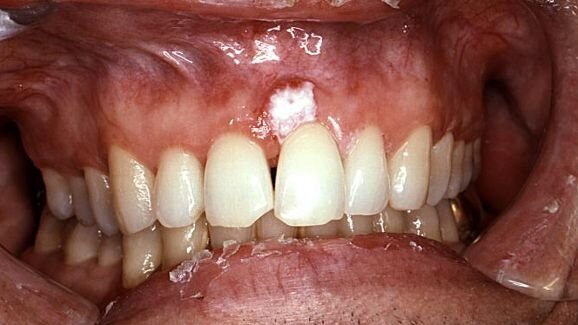

According to the researchers, 30 per cent of mouth lesions turn into cancers. To date, however, there has been no test available to detect accurately which lesions might become cancerous for early treatment.

The newly developed quantitative Malignancy Index Diagnostic System measures the levels of 16 genes that are highly expressed in many cancer types. Their mRNA expression levels are translated via a diagnostic algorithm into a metric scoring system, which quantifies the risk of the lesion becoming cancerous.

In preliminary studies of 299 hospital patients in Norway and the UK, the test detected 91 to 94 per cent of cancer cases from 359 head and neck tissue specimens.

Compared with conventional histopathology, the new test is less invasive because it requires only a 1 to 2 mm piece of tissue and can provide results within less than three hours. Histopathology involves tissue biopsy and pathological examination, may take up to a week to yield results, and detects mouth cancer at a much later stage.